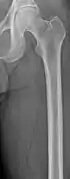

Medical imaging

The diagnostic examination of a person with suspected multiple myeloma typically includes a skeletal survey. This is a series of X-rays of the skull, axial skeleton, and proximal long bones. Myeloma activity sometimes appears as "lytic lesions" (with local disappearance of normal bone due to resorption) or as "punched-out lesions" on the skull X-ray ("raindrop skull"). Lesions may also be sclerotic, which is seen as radiodense.[70] Overall, the radiodensity of myeloma is between −30 and 120 Hounsfield units (HU).[71] Magnetic resonance imaging is more sensitive than simple X-rays in the detection of lytic lesions, and may supersede a skeletal survey, especially when vertebral disease is suspected. Occasionally, a CT scan is performed to measure the size of soft-tissue plasmacytomas. Nuclear Medicine Bone scans are typically not of any additional value in the workup of people with myeloma (no new bone formation; lytic lesions not well visualized on nuclear bone scan).